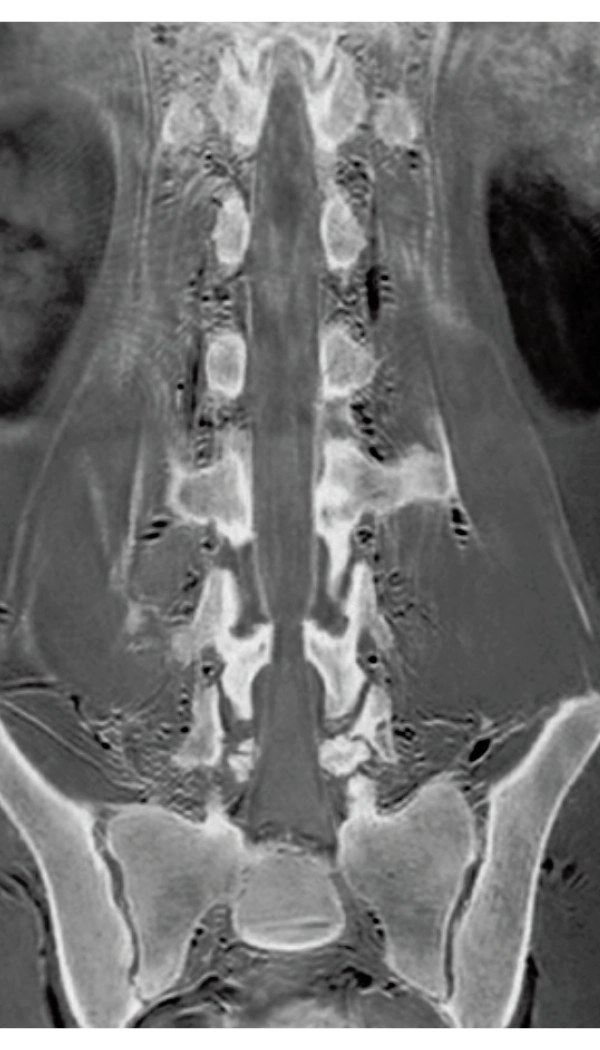

DLR offers 2 options

High Resolution

T2WI, 0.56×0.70×3.0mm, 2:28

3D Bone

0.93×0.93×1.2(0.6)mm

1.1×1.1×1.2(0.6)mm

3DisoFSE T2WI

0.75×0.75×1.1(0.55)mm

MPR COR